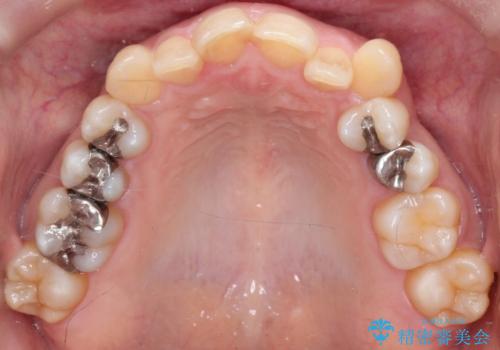

【インビザライン】重度叢生をなおしたい

- 全体的に歯並びをなおしたいことを主訴に来院されました。

上顎前歯が舌側傾斜していたため少し拡大を行いながら非抜歯で治療を行っています。

マウスピースをしっかり使用していただいたので、きれいな歯並びになりました。